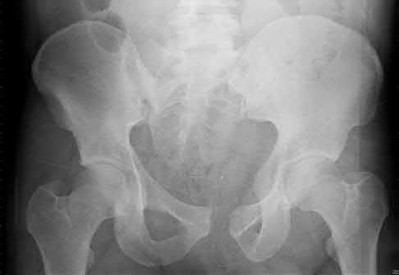

3. # Which of the following is not an appropriate implant for treatment of the fracture seen in Figure A?

5. Sliding hip screw Corrent answer: 5

The image shows a reverse obliquity intertrochanteric hip fracture.

According to the referenced article by Haidukewych et al, unstable peritrochanteric hip fractures have a worse outcome (failed in 9/16 cases) if treated with a sliding hip screw. Two additional factors that were found to have a strong correlation with postoperative failure (nonunion, loss of reduction) were poor reduction and poor implant placement. In this study, fixed angle devices were superior. Intramedullary fixation has the added advantage of a shorter lever arm and less potential for fracture collapse and limb shortening.

The IMN also acts as a medial buttress.

According to Sanders et al, the dynamic condylar screw (DCS) can also be used in subtrochanteric models, but should not be used if extensive comminution is seen, as they reported a high failure rate with DCS in these fractures if highly comminuted. They report a 77% overall union rate with this device.